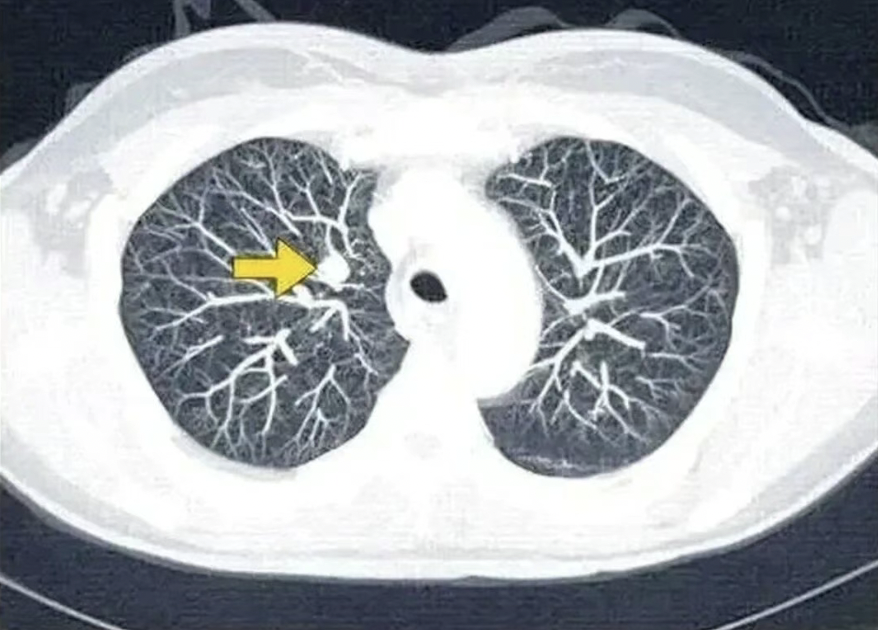

很多人每年只做单位体检的胸片(X光),但胸片的分辨率其实很有限,很多早期肺癌,特别是“磨玻璃结节”这种类型,胸片根本看不清楚,极易漏诊。低剂量螺旋CT是目前国际公认的、筛查早期肺癌的“金标准”,它能发现小于1厘米的微小病灶。